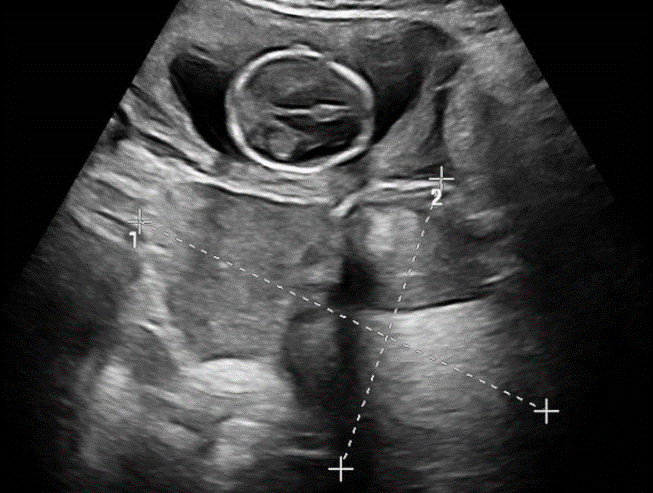

这位孕妇在建立产检档案时意外发现卵巢上的两枚畸胎瘤,由于既往缺乏体检,导致她对这一病情缺乏重视。近期孕妇感觉下腹坠胀明显,复查超声则提示肿瘤增长趋势明显,已经达到了20厘米。为了最大限度地保护母婴安全,在张跃明主任的带领下,妇产科对患者病情进行了全面评估。

面对孕中期合并巨大畸胎瘤的特殊情况,张跃明主任与侯文杰副主任迅速启动科内讨论、制定最优诊疗方案。考虑到传统腹腔镜需3-4个穿刺孔,且肿瘤取出过程耗费大量时间,对母婴安全存在威胁,尤其是麻醉药物对于胎儿的影响。因此,以“超级微创”为出发点、缩短手术时间为前提,最终决定采用单孔腹腔镜手术方式。

单孔腹腔镜是通过人体自然腔道——肚脐实施手术,实现真正的“零疤痕”。通过精细操作成功切除了体内巨大畸胎瘤,术毕通过脐孔成型缝合法,使手术切口“隐形”。科室医疗团队根据孕妇的具体情况和需求,量身定制了适合她身体情况的手术方案。整个手术过程顺利,时间短,术后孕妇恢复迅速,母胎平安。